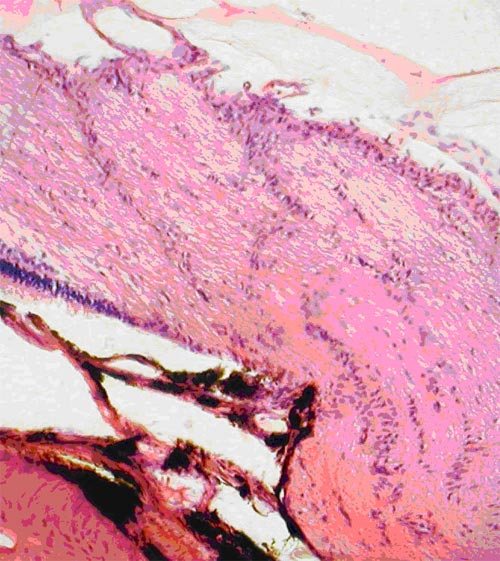

У группы интактных животных (№ 1) проведенные собственные исследования позволили выявить, что в назальной половине сетчатки глаза количество ганглиозных клеток на 20-30% больше, чем в височной половине. В этой группе в обеих половинах сетчатки в слое фоторецепторов и биполяров по направлению к углу задней камеры глаза наблюдалось уменьшение толщины слоев и количества клеток. Обнаружено, что количество крупных клеток в группе интактных животных больше при приближении к цилиарному телу, а мелких - к диску зрительного нерва. В группе интактных животных (№ 1) в ганглиозном слое располагались клетки с ядрами различных размеров. Цитоплазма клеток имела слабо эозинофильную окраску, ядра хорошо прокрашивались гематоксилином в синий цвет (рис. 1).

Интактные кролики. Обычное содержание клеток в сетчатке: 1 - ганглиозный слой, 2 - слой биполярных клеток. Окраска гематоксилином и эозином. Ув.  200

Рис. 1. Интактные кролики. Обычное содержание клеток в сетчатке: 1 - ганглиозный слой, 2 - слой биполярных клеток. Окраска гематоксилином и эозином. Ув. 200

Количество их распределялось следующим образом: всего клеток - 509,67±12,35, из них: мелких - 184,00±5,00; средних - 229,17±12,41; крупных - 96,50±3,58. В норме соотношение: мелкие/средние/ крупные клетки было 36/45/19%. Толщина слоя аксонов ганглиозных клеток при измерении на расстоянии 350 мкм от края решетчатой пластинки, где ход аксонов был еще параллельным сетчатке, равнялась 129,15±1,86 мкм. Слой имел равномерное слабо розовое окрашивание, на его поверхности лежали тонкостенные капилляры (рис. 2).